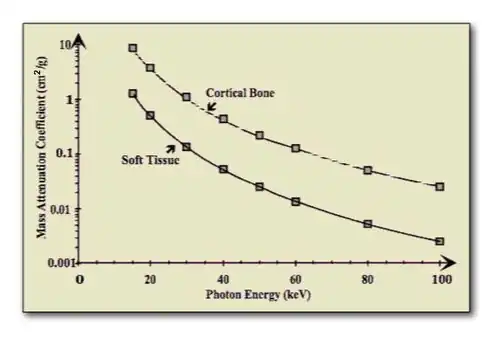

Dual-energy imaging is based on exploiting the difference in the attenuation of tissue and bone at different X- ray energies – see the following figure:

It generally involves acquiring images at two X-ray energies and processing these images to suppress either the bone or the tissue information. A simple mathematical model assumes that monoenergetic radiation is used and no scattered radiation is detected, so that the transmitted radiation intensity through a region of bone and tissue, acquired at a low X-ray energy and following logarithmic transformation, is given by: